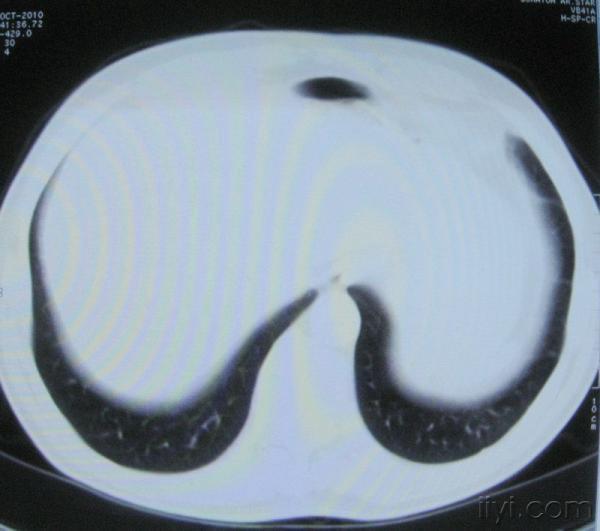

男。60岁,胸片示支气管炎治疗后复查CT。